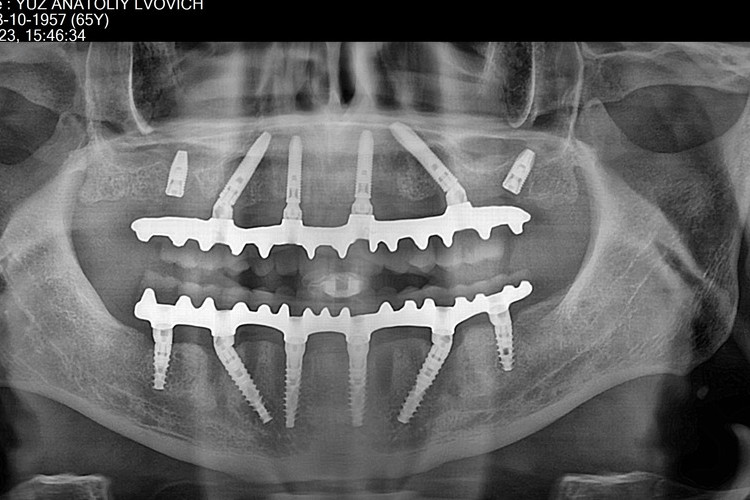

All-on-4 на рентгеновских снимках

![]() |